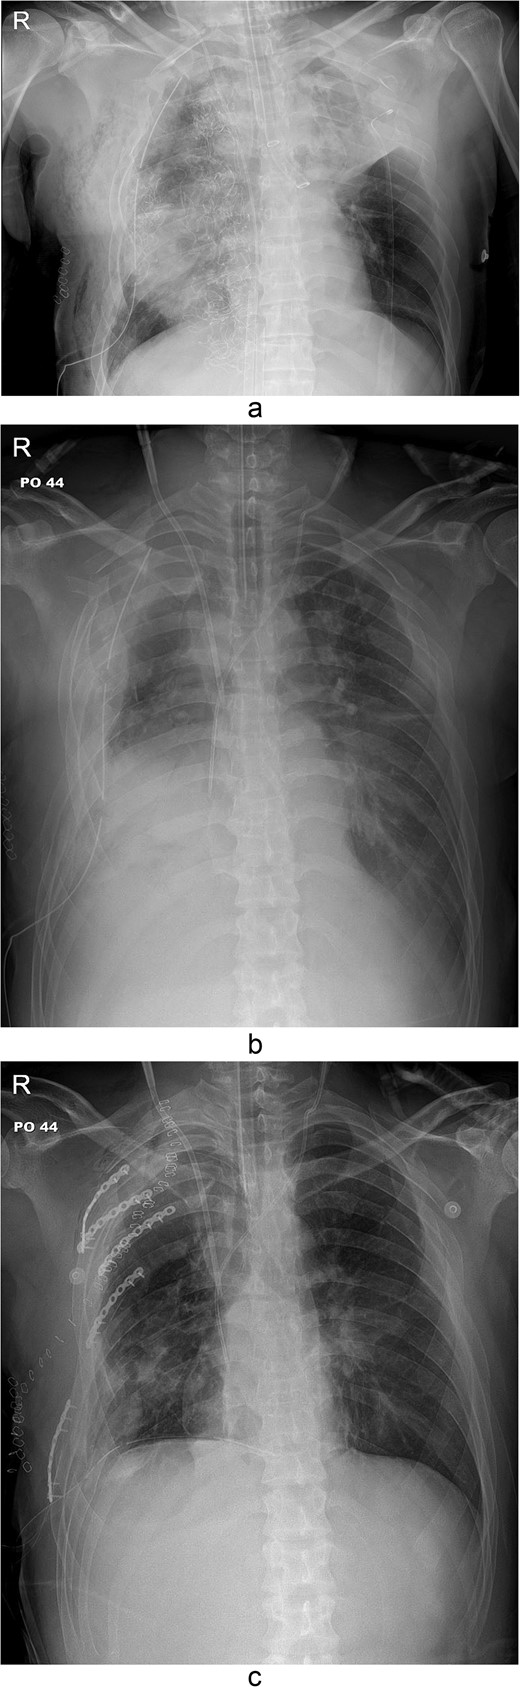

Simple radiographs obtained after each operation. (a) Radiograph after the first operation. Gauze, which is visible as a wavy white line, was packed in the right thoracic cavity. Multifocal opacity was seen in the right lung, and there was left upper lung atelectasis. ECMO catheters were placed in the IVC. (b) Radiograph following the second operation. The right ribcage is narrowed due to displaced fractured ribs. (c) Radiograph after the third operation. Five plates were applied to the fractured ribs.